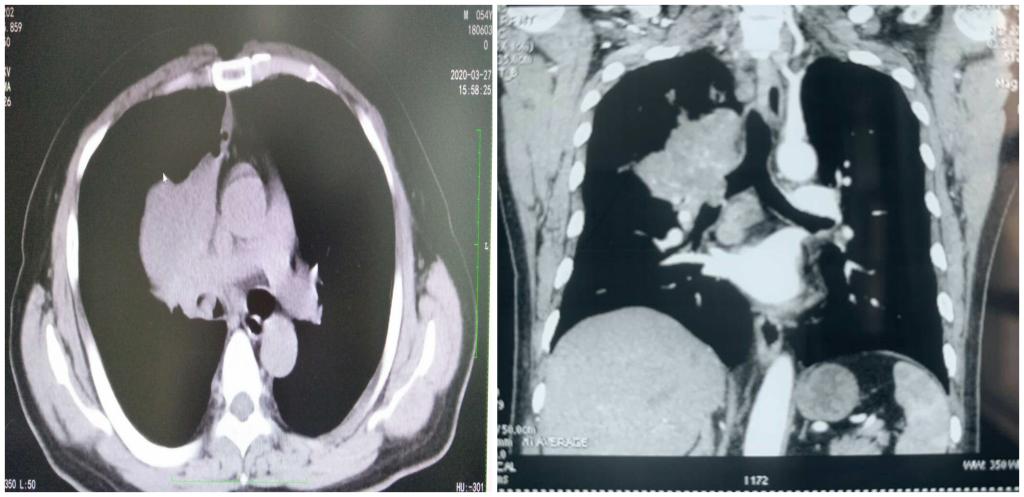

抗疫期间科室积极开展高水平镜下治疗,2月份共开展支气管镜及镜下治疗30余例,老赵就是其中的一位患者。他是西安市人,长期大量吸烟,因“间断咳痰、痰中带血、气短3月”就诊于当地医院,行胸部CT提示右肺门肿块,右主支气管新生物,辗转多家医院均因疫情影响内镜检查暂时停诊而无法诊治,但气短却日渐加重,后经人介绍求诊于我科,科主任张志惠看过影像学检查,考虑气道新生物已明显阻塞主支气管,血气分析提示严重低氧,影响患者通气,必须及时打通阻塞的气道挽救生命。遂在充分评估手术风险并取得家属同意后,迅速安排支气管镜检查,并在支气管镜下行气道肿瘤切除手术,经圈套器、氩气、冷冻等多种措施,低氧迅速改善,术后患者气短症状明显减轻。这是凤城医院呼吸科开展的首例大气道巨大肿瘤消融切除术,也是呼吸与危重症医学科全体人员在抗疫过程展示的实力和态度。